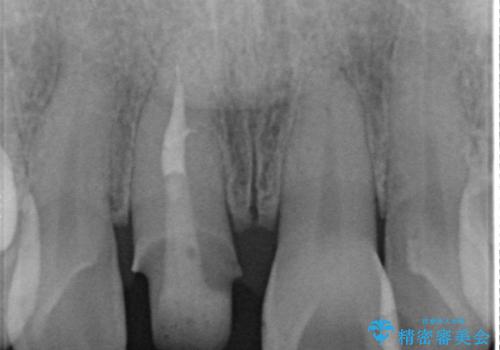

- 前歯の変色の改善を希望され来院されました.

以前に神経が死に、根管治療を行った歯の変色が認められたためセラミックによる審美補綴治療を計画します。

神経の死んでいる歯について

神経治療を行い補綴(かぶせもの)治療を行わないと、変色が目立ち審美障害を起こすことがあります。